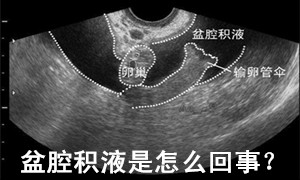

盆腔积液是怎么回事? 因为盆腔是腹腔在全身最低的部位,当有渗出液或漏出液时都会引流到盆腔,从而形成盆腔积液。大多数盆腔积液是由于炎症引起,即由慢性盆腔炎症渗出所致。盆腔积液的主要致病因有:月经期不注 意卫生、邻近器官炎症蔓延、产后、流产后感染、妇科手术后感染等。也有少数因宫外孕破裂、黄体破裂、盆腔脓肿、巧克力囊肿、卵巢癌引起。

+已赞什么是盆腔积液? 南京妇儿堂妇科专家专业指出:盆腔积液,分为生理性和病理性,生理性的盆腔积液多发生在妇女排卵后或早孕期。病理性盆腔积液可发生在子宫内膜发炎后,内膜组织肿胀的细胞中渗出的略黏稠的液体,被周围组织包裹所渐渐形成的囊性包块。是盆腔存在炎性渗出物,如果不加以治疗的话,会慢慢长大,药物就不容易消除了,需要介入物理治疗。